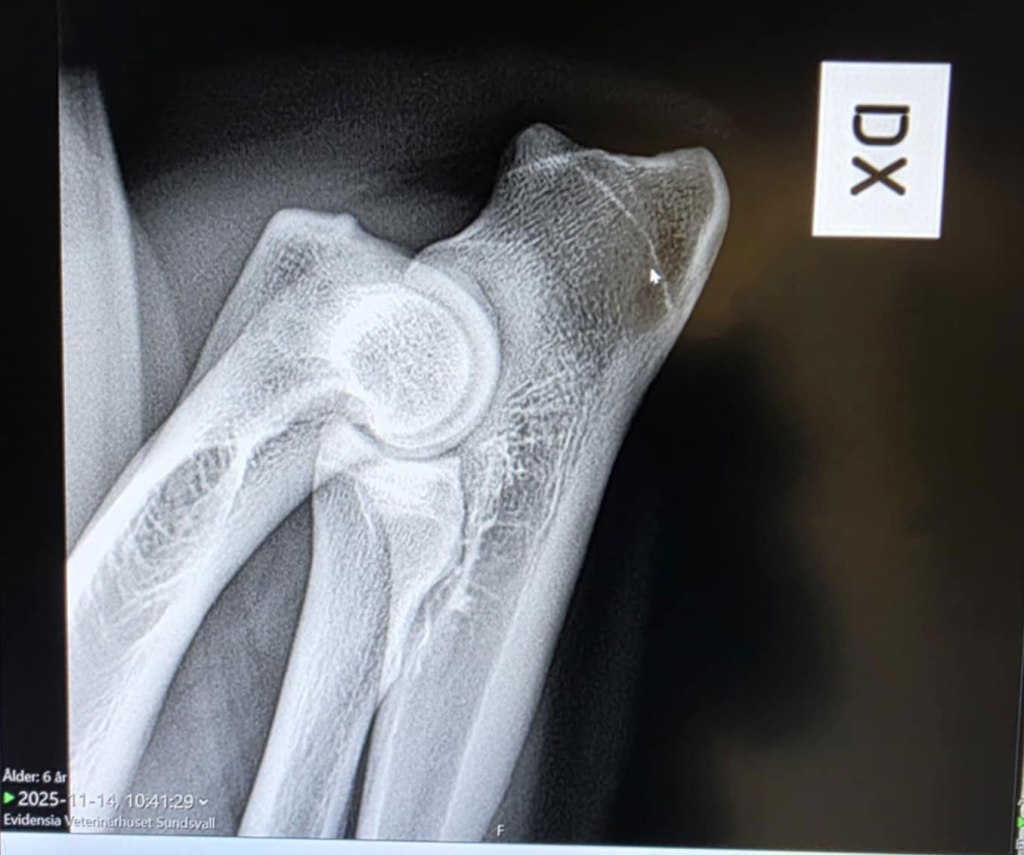

När vi röntgade hans ED hade vi i ärligheten lite ångest utifrån hans historia med sitt bakben där han var skadad i princip i två år om man räknar in hans långa rehabiliteringsperiod. Skulle inte vara konstigt att man ev hittade exempelvis någon form av artos, han är ju dessutom något till åren kommen när röntgen genomfördes. Men när vi såg bilderna på Veterinärhuset i Sundsvall så kunde till och med två riktiga amatörer som jag och Kenth se att de förmodligen

var utan anmärkning och det var också det svar vi senare fick efter avläsningen hos SKK.